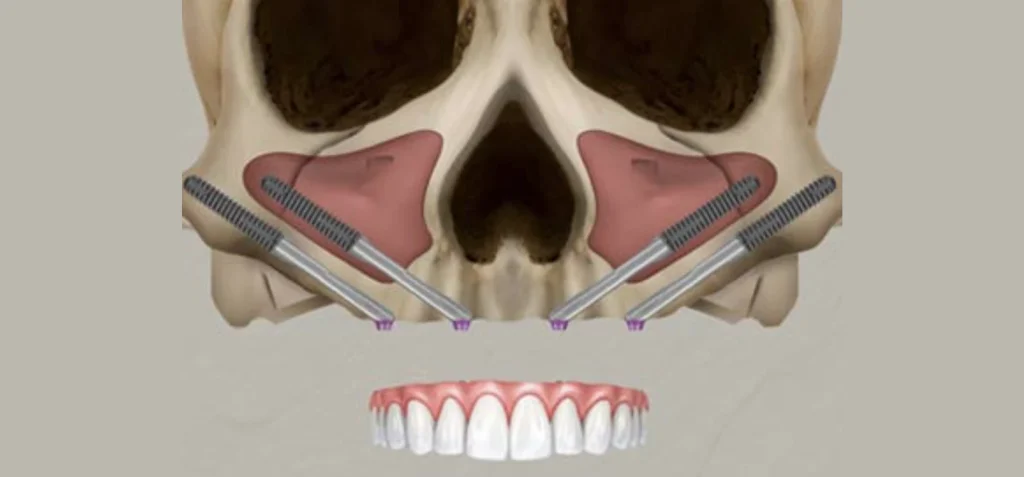

Un implant zygomatique est plus long qu’un implant en titane classique. Il mesure de 3 à 5 cm. L’os des pommettes est d’excellente qualité, il ne se résorbe pas. Son volume osseux est généralement suffisant. Chaque pommette peut recevoir un ou deux implants. La partie de l’implant visée dans l’os zygomatique est rugueuse pour une meilleure accroche et cicatrisation osseuse, l’autre partie qui traverse le sinus et la muqueuse buccale est lisse pour éviter de fixer les bactéries. Le col de l’implant est angulé à 55 degrés pour rattraper l’axe d’insertion. Un pilier (violet) est vissé dans l’implant. Son épaisseur varie de 1 à 3 mm. Il est choisie en fonction de l’épaisseur de gencive. La prothèse se visse sur le pilier.

Si l’atrophie osseuse est seulement postérieure, 2 implants zygomatiques postérieurs suffisent couplés à 2 implants antérieurs classiques, on parle de réhabilitation prothétique fixe sur 4 implants de type zygomatique hybride. Dans ce cas de figure, l’implant zygomatique est positionné en position basse de manière à garder un volume osseux disponible supérieur sur le zygoma pour placer un 2 ème implant zygomatique à distance si besoin.

Si l’atrophie osseuse concerne toute la mâchoire, 4 implants zygomatiques sont nécessaires. Ils sont placés de manière à sortir sous les incisives latérales et les 2 ème prémolaires. L’implant supérieur longe à distance du rebord orbitaire, l’implant inférieur chemine sur la plus grande longueur d’ancrage osseux quelques millimètres plus bas. Le nerf infra-orbitaire responsable de la sensibilité para-nasale et jugale doit être respecté lors de la pose implantaire au risque de trouble de la sensibilité. On parle de réhabilitation prothétique fixe sur 4 implants zygomatiques ou quad zygomatiques.